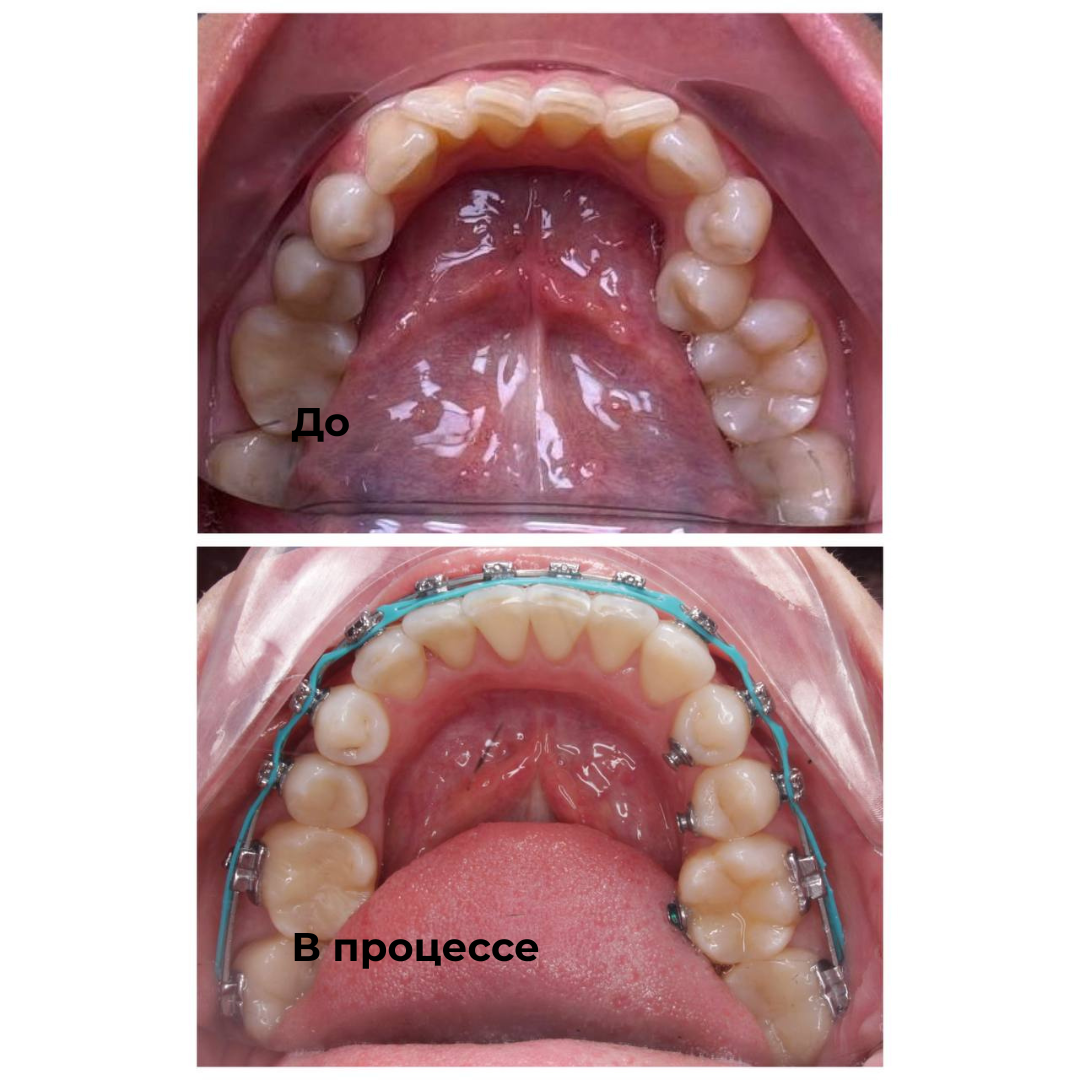

Такие результаты получают наши пациенты после лечения

Каждый случай - индивидуальный, но результат один: ровные зубы